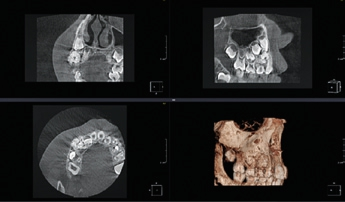

Es ist allgemein bekannt, dass bei der Akquisition einer digitalen Volumentomographie (DVT) mit Artefakten wie Aufhärtungen und Abschwächungen gerechnet werden muss. Obgleich die Rekonstruktionszeit erheblich reduziert wurde, die Auflösung der Aufnahmen immer höher wird und die Bildqualität ständig zunimmt, stellen Artefakte ein stets präsentes Problem in der Verfahrenskette dar. In manchen Fällen machen diese Artefakte gerade für den Ungeübten eine Bildanalyse unmöglich. In der Literatur werden Artefakte wie z. B. Auslöschungs- und Aufhärtungsartefakte beschrieben (Abb.6 u. 7). Sie sind technisch bedingt, während eine andere, sehr wichtige Ursache dieser Artefakte im Patienten selbst zu sehen ist. Da die Belichtung in der Regel mehr als ein paar Sekunden dauert und der Patient im Gegensatz zu der entwicklungsbezogenen These kein statisches Objekt darstellt, kann es passieren, dass er seinen Kopf während der Aufnahme bewegt. In diesem Fall findet man im rekonstruierten Datensatz sogenannte Bewegungsartefakte, die die Bildqualität erheblich beeinflussen können (Abb. 8).

Durch weitere Rechenprozesse können die Daten auf verschiedenste Weise dargestellt werden. Die multiplanaren Rekonstruktionen (MPR) stellen die sinnigste Weiterverarbeitung der Daten dar. Hierbei wird das Volumen durch senkrecht zueinander stehende Ebenen zerlegt, wodurch die Ansichten axial, sagittal und koronal erzeugt werden, ergänzt durch die oberflächengerenderte Ansicht (Abb. 9). Das Angebot entsprechender Bildbearbeitungsprogramme ist vielfältig, zumeist wird das DVT-Gerät mit einer adäquaten Software installiert und eingerichtet – ab diesem Zeitpunkt ist nun der/die Anwender/-in gefordert. In Deutschland ist die Absolvierung eines DVT-Kurses vor Inbetriebnahme eines DVT-Gerätes gesetzlich vorgeschrieben.